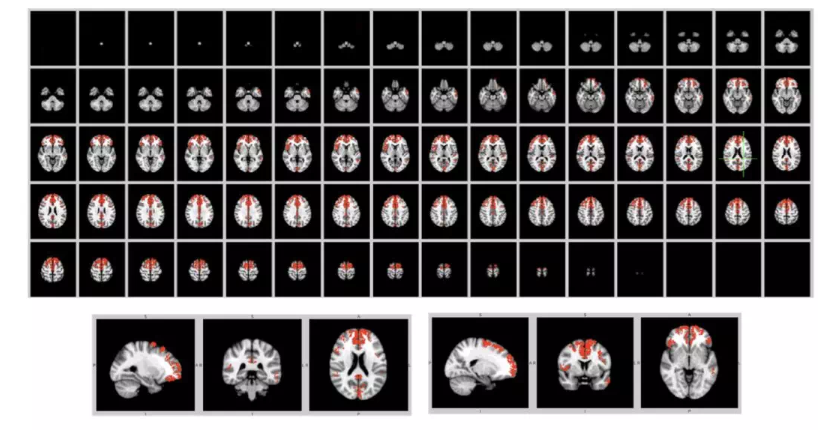

这里给出了 148 大脑区域中的 24个大脑区域 embedding的可视化结果,患者是红色,正常人是绿色,加上 graph infomax 的损失之后,正常人和患者的有些大脑区域更加线性可分。

在大脑的 148个区域中,我们发现了 31个比较线性可分的大脑区间,在上图中的标记为红色。